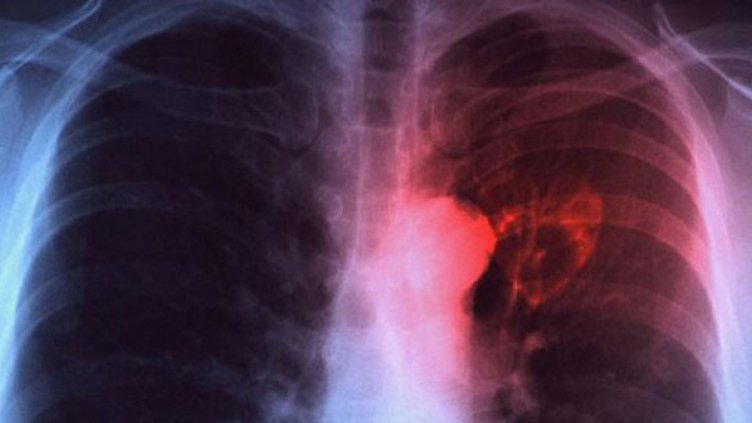

Д-р Наталия Спиридонова успокои хората, като обясни, че действително има случай на болно дете от училището, но туберкулозата е на вътрешните лимфни възли и бактерията не се отделя в околната среда. Препоръчано е всички, които са били в контакт с детето, да си направят манту.

"Отговорността за изпълнението на предписанието е на директора", подчерта тя пред bTV.